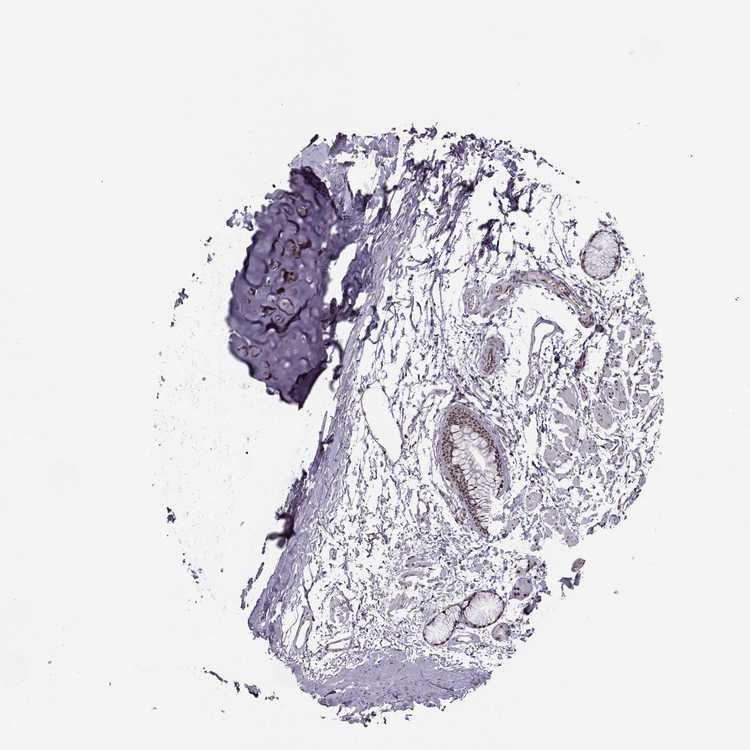

SOFT TISSUE 1 - Antibody stainingi

Antibody staining in the annotated cell types in the current human tissue is reported as not detected, low, medium, or high, based on conventional immunohistochemistry profiling in selected tissues. This score is based on the combination of the staining intensity and fraction of stained cells.

Each image is clickable and will lead to virtual microscopy that enables deeper exploration of all samples and also displays staining intensity scores, fraction scores and subcellular localization as well as patient and tissue information for each sample.

Antibody HPA077597

Fibroblasts Low

SOFT TISSUE 2 - Antibody stainingi

Fibroblasts Medium

Peripheral nerve Low